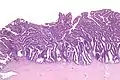

Micrograph of a villoglandular adenocarcinoma the cervix. H&E stain.

The name of the lesion describes it microscopic appearance. It has nipple-like structures with fibrovascular cores (papillae) that are long in relation to their width (villus-like), which are covered with a glandular pseudostratified columnar epithelium.